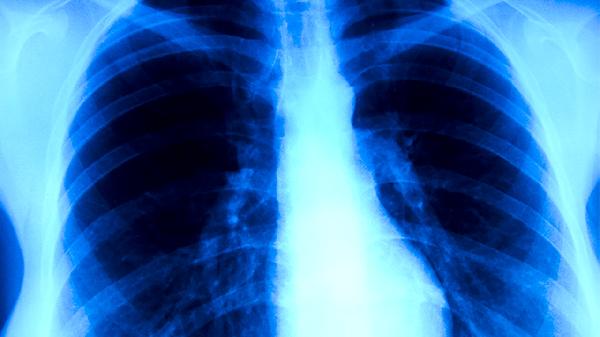

良性肺结核主要指肺部病灶稳定、无活动性炎症的结核病变,这类患者痰液涂片和培养结果多为阴性,结核分枝杆菌未通过飞沫传播。世界卫生组织指出,痰菌阴性肺结核的传染性不足痰菌阳性者的百分之五。患者日常咳嗽、打喷嚏时排出的飞沫中病原体载量极低,与这类患者共处一室或短暂接触通常不会导致感染。临床观察显示,多数良性肺结核患者即使未经隔离治疗,其密切接触者的结核菌素试验阳性转化率与普通人群无显著差异。

当良性肺结核患者合并支气管扩张、慢性阻塞性肺病等继发感染时,可能出现痰菌假阴性情况。部分处于结核病灶液化前期或合并免疫缺陷的患者,痰菌检测结果可能存在波动。这类情况下,患者呼吸道分泌物中可能间歇性排出结核杆菌,通过长时间密切接触存在传播可能。研究数据表明,合并糖尿病的结核病患者痰菌转阴后复发率可达普通患者的两倍。

肺结核患者应定期复查痰涂片和胸部影像学检查,即使诊断为良性肺结核也需完成全程抗结核治疗。日常注意保持室内通风,咳嗽时用纸巾遮掩口鼻,痰液需消毒处理后丢弃。接触者出现持续咳嗽、低热、盗汗等症状时应及时进行结核筛查。接种卡介苗可降低儿童重症结核病发生概率,但无法完全预防感染。